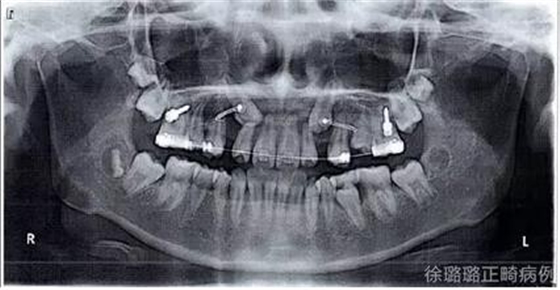

X 線檢查:替牙列,上頜雙側(cè)尖牙埋伏阻生(含牙囊腫),四顆第三恒磨牙牙胚存在。

前牙 CT 檢查:上頜雙側(cè)尖牙埋伏阻生——雙側(cè)尖牙的牙冠均在側(cè)切牙根方的唇向位。

CT 片結(jié)果顯示,上頜雙側(cè)側(cè)切牙與尖牙位置較近,因此早期沒有粘結(jié)雙側(cè)側(cè)切牙托槽,以防止正畸加力對牙齒造成根尖吸收。

咬合分析:建立了雙側(cè)磨牙及尖牙 I 類關(guān)系;前牙覆牙合、覆蓋關(guān)系正常;上下中線基本與面中線一致。

該病例通過口腔外科導(dǎo)萌術(shù)與正畸的聯(lián)合治療,非拔牙矯治上頜雙側(cè)尖牙埋伏阻生。患者矯治結(jié)束后,面部左右對稱,凹面型得到改善,上下唇突度未因非拔牙矯治造成進(jìn)一步前突,顴骨突出得到掩飾,下頜偏斜得到糾正,上下中線基本與面中線一致;上頜前牙突、下牙列擁擠得以解除;雙側(cè)上頜尖牙成功導(dǎo)萌,磨牙、尖牙建立了中性關(guān)系,前牙覆牙合、覆蓋關(guān)系正常。